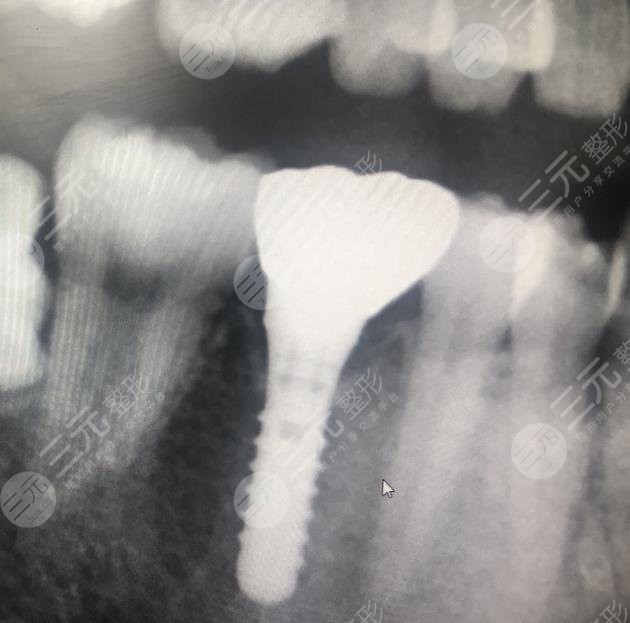

手术项目: 种植牙

来到医院之后,医院的整体环境是比较好的,而且医生技术水平也比较高,在进行手术的时候给我注射了麻药,所以说种植牙手术不会疼痛,大概没有多长时间,整个种植牙手术就完成了,接下来就是护理的时间了,做完牙齿护理,只要牙齿恢复到正常的状态,就说明牙齿种植很成功,在恢复期间可以说是比较漫长的过程,一定要做好术后护理,这样对于伤口的维护才能够带来好的果。

我当时的时候就是特别的仔细小心辛辣的食物不敢吃也不能吃坚硬的食物,大概过了三个多月的时间整个种植牙的果就比较好了,而且我还特意到医院去进行了复查,医生也认认真真的检查了我的牙齿情况,牙龈组织都是较为健康的,没有任何的炎症出现,而且种植牙也较为的牢固稳定,果比较好,就跟我自己的真牙一样,没想到在这么短的时间内就让我拥有了像真牙一样的牙齿,较为开心。